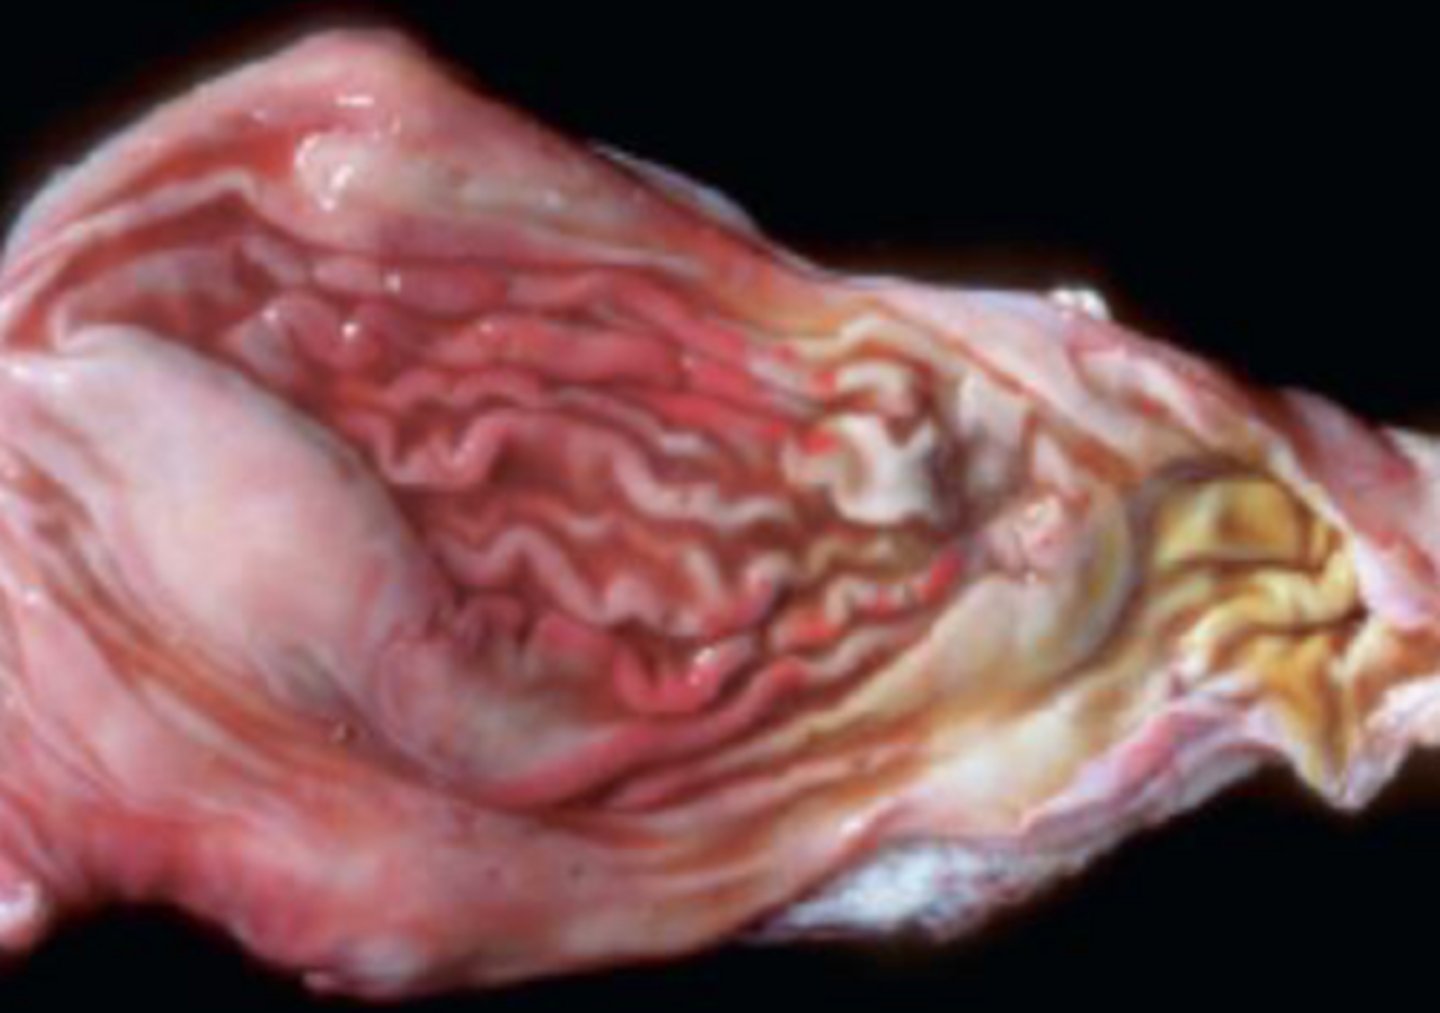

Canine gastric dilation and volvulus (GDV)

- Large breed/ deep chested

Identify the pathology?

Fundus twists and greater curvature is displaced ventrally and duodenum will be moved dorsally and caudally

Explain the pathology of GDV?